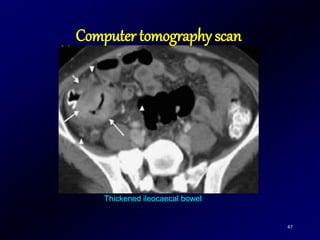

Computer tomography scan

47

Thickened ileocaecal bowel